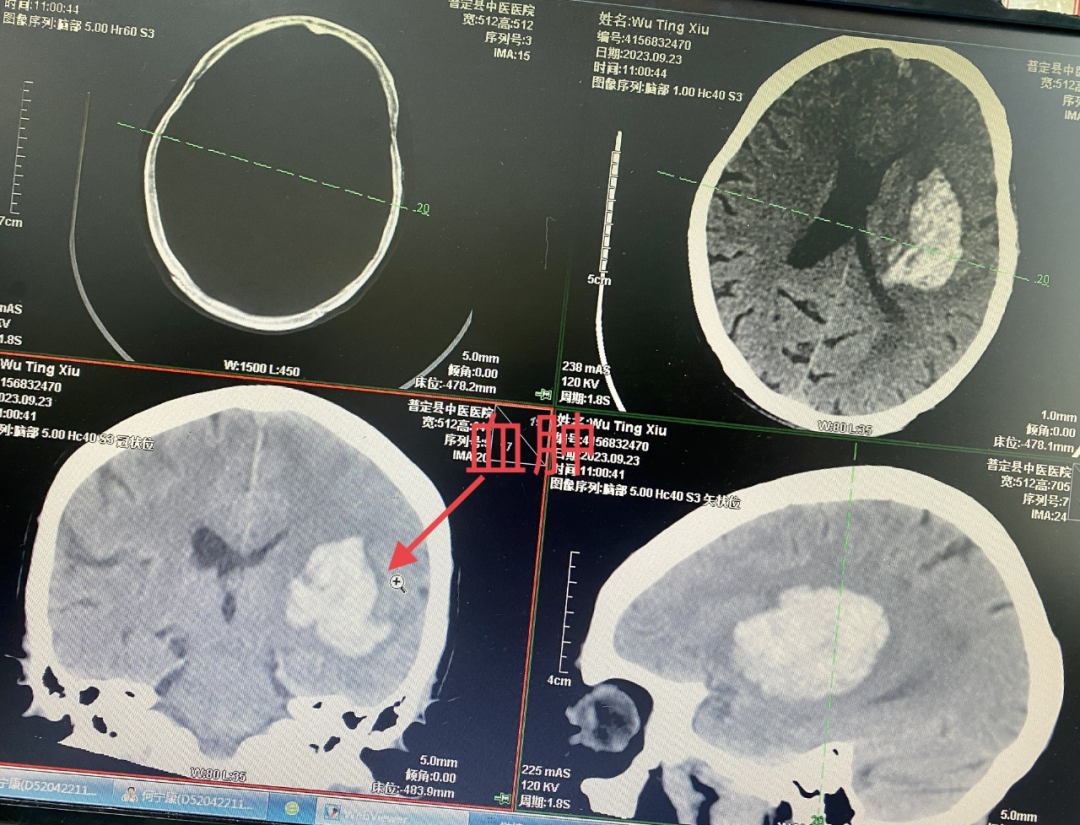

73岁的吴奶奶,入院前一个小时突然出现言语不利伴右侧肢体无力,被家属紧急送到我院就诊,入院时意识不清,嗜睡,右侧肢体偏瘫,查头颅CT提示:左侧基底节区出血,量约30+ml,家属考虑患者年龄大,既往基础疾病多,体质瘦弱,手术风险高,要求药物非手术观察治疗。住院期间患者意识障碍加重呈浅昏迷状,鼾样呼吸,剧烈呕吐,再次复查头颅CT提示出血无明显增加,血肿腔周围水肿加重,外二科神经外科组医生当机立断,建议行手术治疗,充分综合考虑患者的身体情况,详细向家属沟通各种手术方式,为缩短麻醉时间,减少手术创伤,降低手术风险,手术方式建议选择微创颅骨钻孔血肿穿刺置管引流术或小切口小骨窗开颅血肿清除术,在告知各种术式利弊及风险后,家属最终决定选择小切口小骨窗开颅血肿清除术。

入院时CT

入院6小时CT